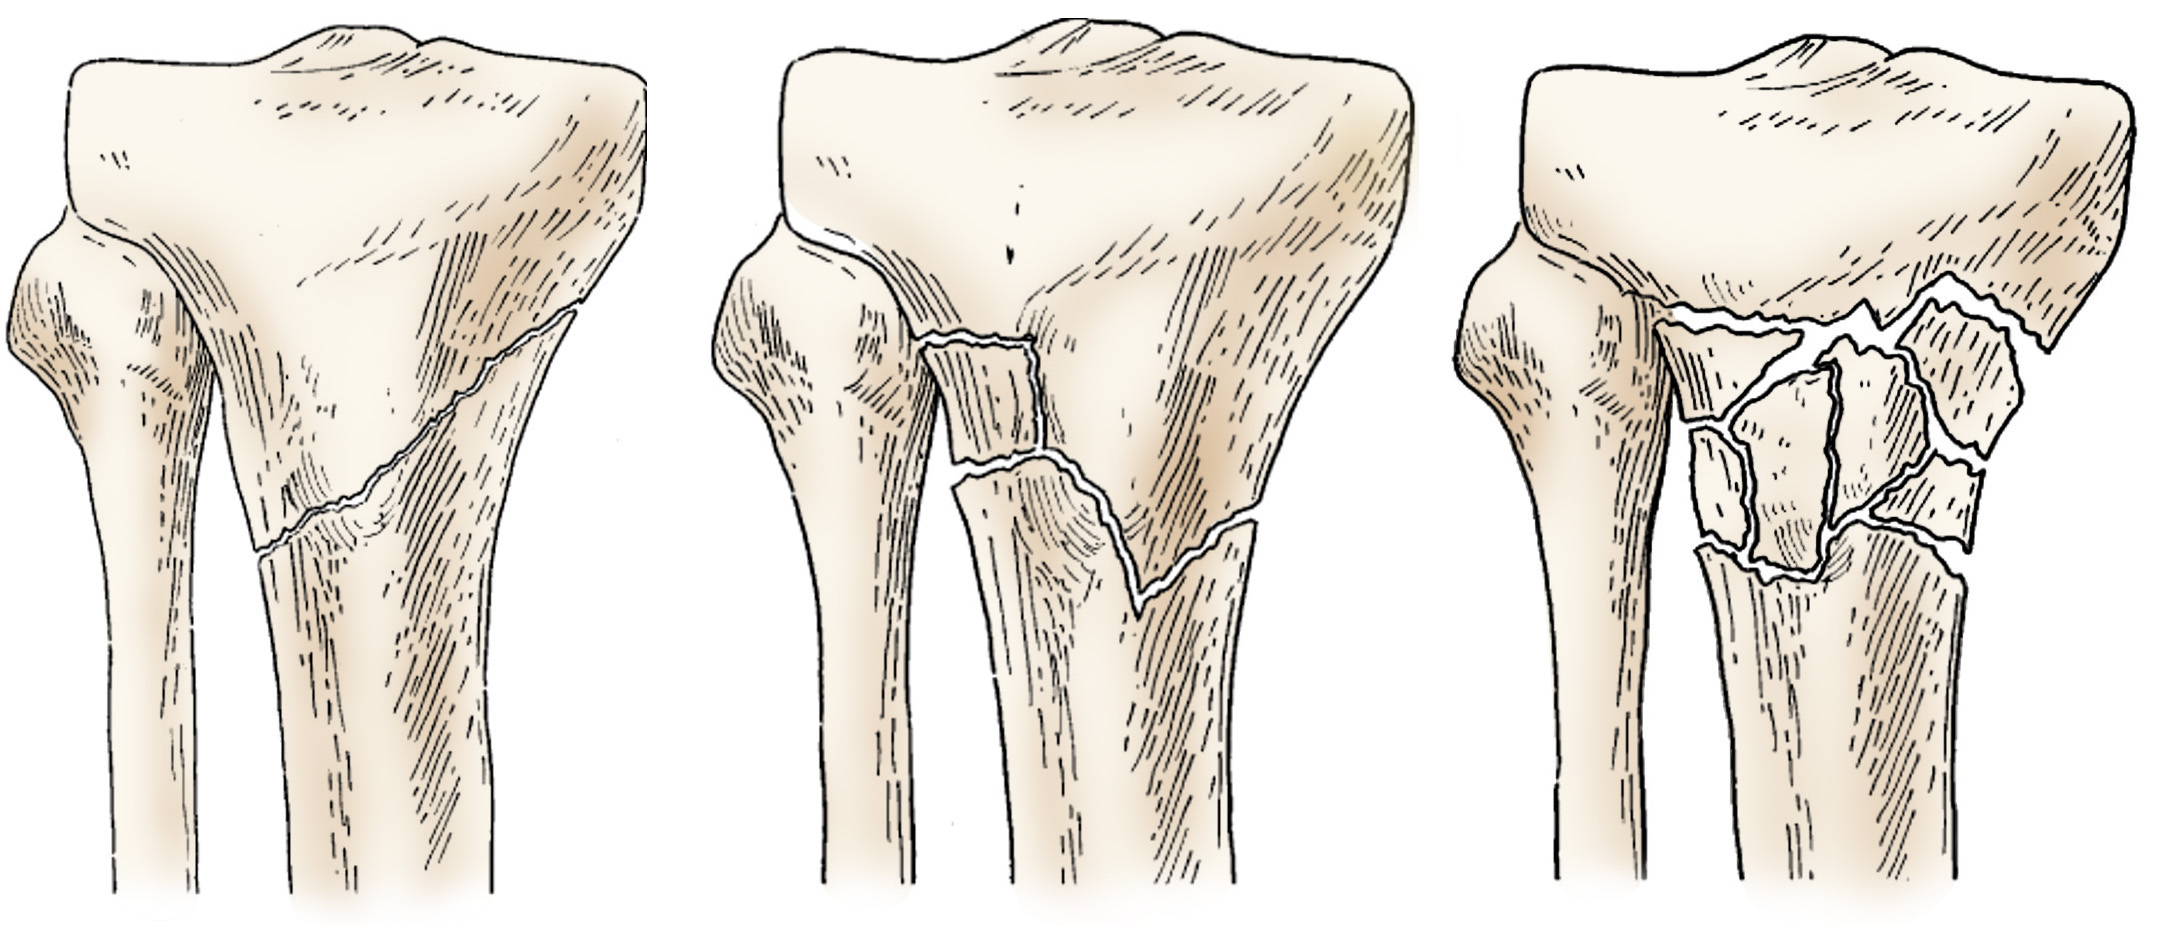

Illustration of different proximal tibia fractures

Examples of different types of proximal tibia fractures.

Reproduced and modified from Bono CM, Levine RG, Juluru PR, Behrens FF: Nonarticular proximal tibia fractures: treatment options and decision making. J Am Acad Orthop Surg 2001; 9:176-186.

There are several types of proximal tibia fractures. The bone can break straight across or into many pieces (comminuted fracture).

Sometimes these fractures extend into the knee joint and separate the surface of the bone into a few (or many) parts. These types of fractures are called intra-articular or tibial plateau fractures.